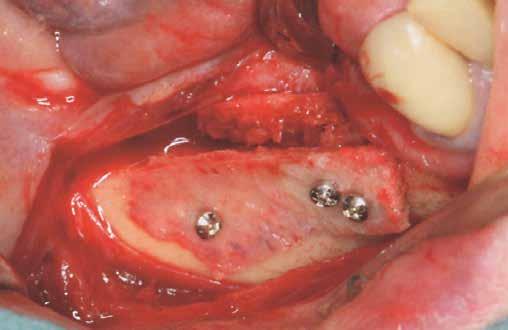

1. c ábra: Vertikális augmentáció két csontlemez bukkális és linguális rögzítésével, oszteoszintézishez használt csavarokkal (Ustomed, Tuttlingen, Németország).

1. d ábra: A lemezek közötti rések kitöltése tömörített szivacsos csonttal.